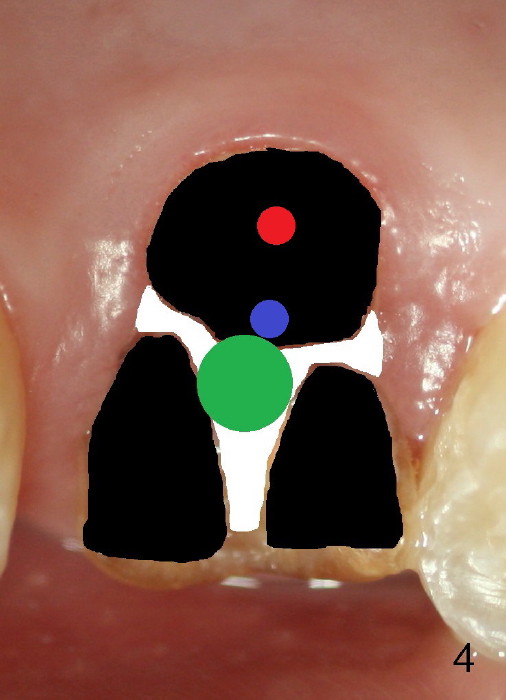

The 1st approach is used for the following case: a 46-year-old man with #14 (Fig.1). The root stumps are large and relatively close to each other (Fig.2 mirror view) so that when the roots are extracted (Fig.3 black), the septum is narrow (white). A 1.2 mm pilot drill penetrates the septum (red).

By the time a 2.6 mm bone expander is used, the septum starts to break off (Fig.4 green). The osteotomy site has to be changed: first to the palatal slope of the palatal socket (red) with the coronal end of the drill leaning buccally. Suddenly a better idea occurs: new osteotomy remains in the palatal socket, but as buccally as possible (blue) and finishes with rounded tapered osteotomes 2-4 mm at ~17 mm deep. The coronal end of the osteotomes is controlled to be positioned in the center of the socket (Fig.5 blue).